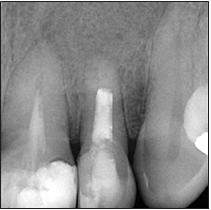

Paciente sexo femenino de 54 años de edad acude a consulta por presencia de fistula en el sector anterior del maxilar, con 15 días de evolución. Durante la anamnesis refiere tener un tratamiento endodóntico de 15 años de antigüedad en el diente 2.2; el mismo tuvo un procedimiento quirúrgico hace 10 años. A la exploración clínica se observó una fístula que se corroboró mediante fistulografía asociada al diente 2.2. La paciente no manifiesta dolor, está asintomática a la palpación y percusión, se realizó un sondaje periodontal obteniendo 3 mm de profundidad. Radiográficamente se observa una zona radiolúcida difusa periapical, cu- briendo el área del diente 2.2, con aproximadamente 13 mm de diámetro, obturación completa del canal radicular, ápice abierto y restauración coronal desadaptada. (Fig.1)

Figura 1. Radiografía periapical inicial.